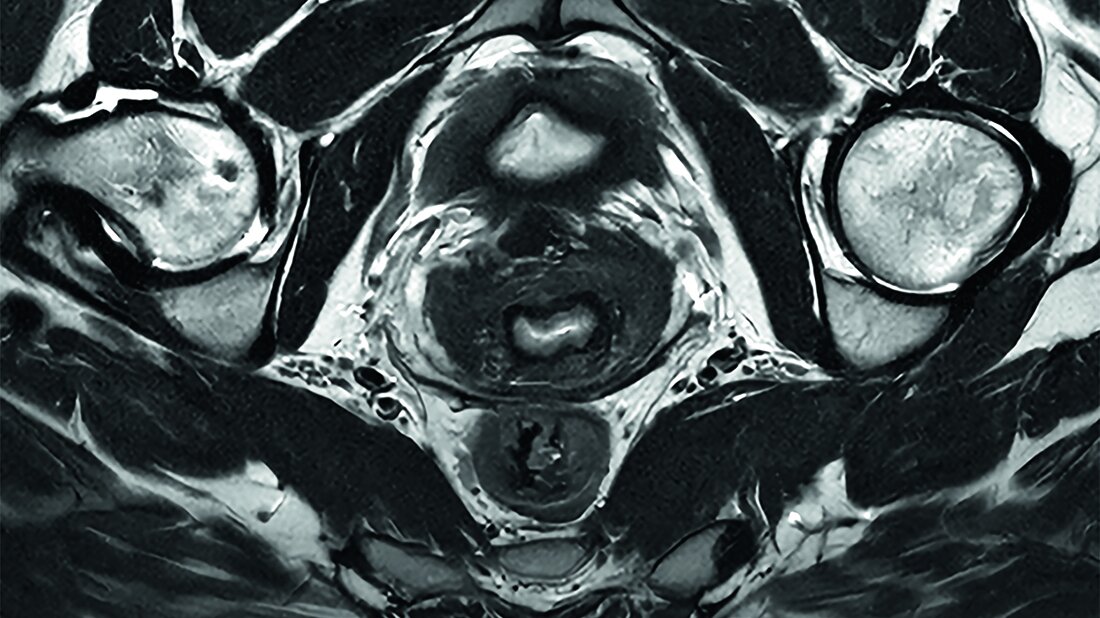

Diese Technologie der nächsten Generation erweitere die KI-gesteuerte Workflow-Effizienz und verbessere die Bildqualität im gesamten Philips BlueSeal MR-Portfolio, einschließlich bereits bestehender Systeme, betonte das Unternehmen. Auf dem ECR 2025 fand auch die europäische Premiere der neuesten Generation des 1.5T BlueSeal MR-Scanners mit komfortabler 70-cm-Öffnung im heliumfreien Betrieb statt. „Mit SmartSpeed auf unserem BlueSeal-Scanner haben wir die Untersuchungszeit für eine Ganzkörperuntersuchung von 75 auf 60 Minuten reduziert, sodass zwei Patienten mehr pro Tag gescannt werden können“, sagte Wayne Picker, Vizepräsident für klinische Technologie bei Prenuvo, Inc. Mit der neuesten Version der Bedienoberfläche – MR Workspace R12 – hat Philips einen „Zero-Click“-Workflow vorgestellt, der den gesamten Bildgebungsprozess von der Auswahl der Systemparameter bis zur Berichterstellung nahtlos steuern soll. Das Herzstück von SmartSpeed Precise ist die Anwendung zweier KI-Modelle in der Bilddatenrekonstruktion, die eine 80-prozentige Steigerung der Bildschärfe ermöglichen soll und die diagnostische Genauigkeit weiter verbessere. Zu den weiteren Innovationen gehöre Smart Reading, die erste und branchenführende Lösung, die eine cloudbasierte, KI-gestützte quantitative Berichterstattung integriere. Smart Reading nutze modernste KI-Plattformen wie icobrain (icometrix) für die Neurologie – einschließlich automatischer Erkennung der mit Alzheimer assoziierten Anomalien – und QP-Prostate (Quibim) für die fortgeschrittene Prostatakrebsdiagnostik.